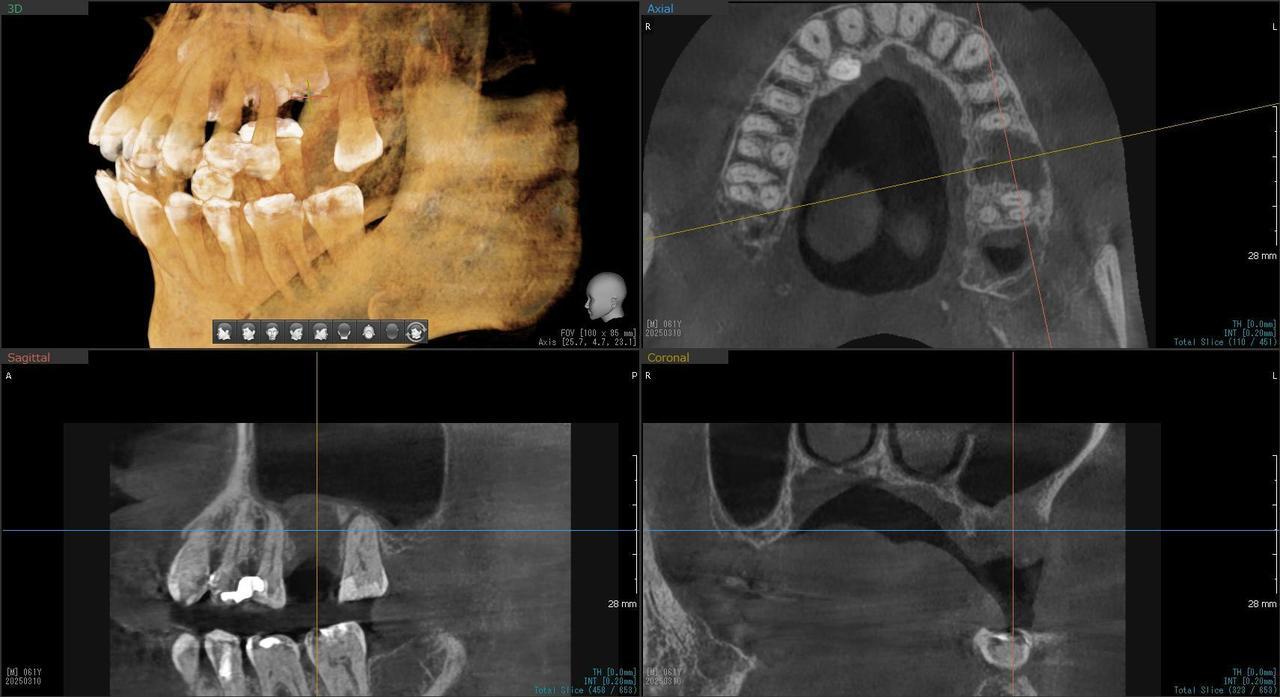

1.左上3番 インプラント抜歯即時埋入即時荷重(手術当日に抜歯を行い、当日に仮歯を入れています。)、左上4番 3ユニット式ブリッジが入るまでの暫間インプラントを埋入して当日に仮歯の装着。 左上5 既存骨3mmのグラフトレスサイナスリフト。最終補綴は、3ユニットジルコニアブリッジで治療を終えた症例

Before

枚方市のインプラントの症例

After

E・S様 女性 60代

患者様の症状としては、左上5番の排膿と重度の歯の動揺、重度の骨吸収、左上3番、中程度の骨吸収と中程度の歯の動揺、自発痛がありました。

治療法としては、左上3456にブリッジ治療が行われていたが、左上5の骨吸収と排膿を認めるために抜歯を行った2か月後に、患者様は、インプラント治療を希望。左上3の骨吸収と動揺も認めていたために、左上3を保存しても将来的な抜歯が予想されたため、左上3抜歯しての左上345の3ユニット式ブリッジ治療の計画を立てインプラント手術を行っています。患者様は、前歯がないことを気にされていたため、左上3番の抜歯と同時の仮歯製作と左上4番暫間インプラントにての仮歯製作を手術と同時に行っています。また、左上3番の歯肉退縮を予防するために、ご自分の歯の一部を温存するルートメンブレンテクニックを行っています。左上5に関しては、既存骨が3mm程度しかないので、グラフトレスサイナスリフトを施行して、表面の骨吸収した部分に骨補填材填入して、ボリュームを維持させていただいています。最終的な3ユニットブリッジは、ジルコニアで製作しています。補綴物の製作に関しては、オールデジタルで行っています。

治療結果は、患者様の希望通り、見えるところの歯がない状態なく、治療を終えることができたことと、また、グラフトレスサイナスリフトを施行することにより、従来のサイナスリフトを施行した場合と比較して、6時か月以上早く治療を終えることができたことと、ルートメンブレンテクニックを行うことで、歯肉退縮を少なくでき、自然な見た目で、最終補綴物を装着できました。従来のGBRやサイナスリフトを行わなかったことにより、短時間で、低侵襲に治療を終えることができ、審美面と機能面の回復を行うことができました。

治療の期間・回数:4か月、10回

治療の価格:814,000円(税込)

治療費の内訳:インプラント基本料(フィックスチャー及び手術費用、投薬費用、レントゲン費用、インプラント上部費用(アバットメントおよびジルコニアクラウンの費用用)右上3番5番 330000円×2 660000円(税込み)オプション費用 右上5グラフトレスサイナスリフト費用 33000円(税込み) 右上3抜歯即時荷重費用 33000円(税込み) 暫間インプラント費用 0円

治療のリスクや副作用:手術後に、痛みや腫れ、出血、合併症などを引き起こす可能性があります。噛む感覚がご自身の歯と異なる場合があります。見た目がご自身の歯と異なる場合があります。手術後にメインテナンスを継続しないと、インプラントが抜け落ちる可能性があります。